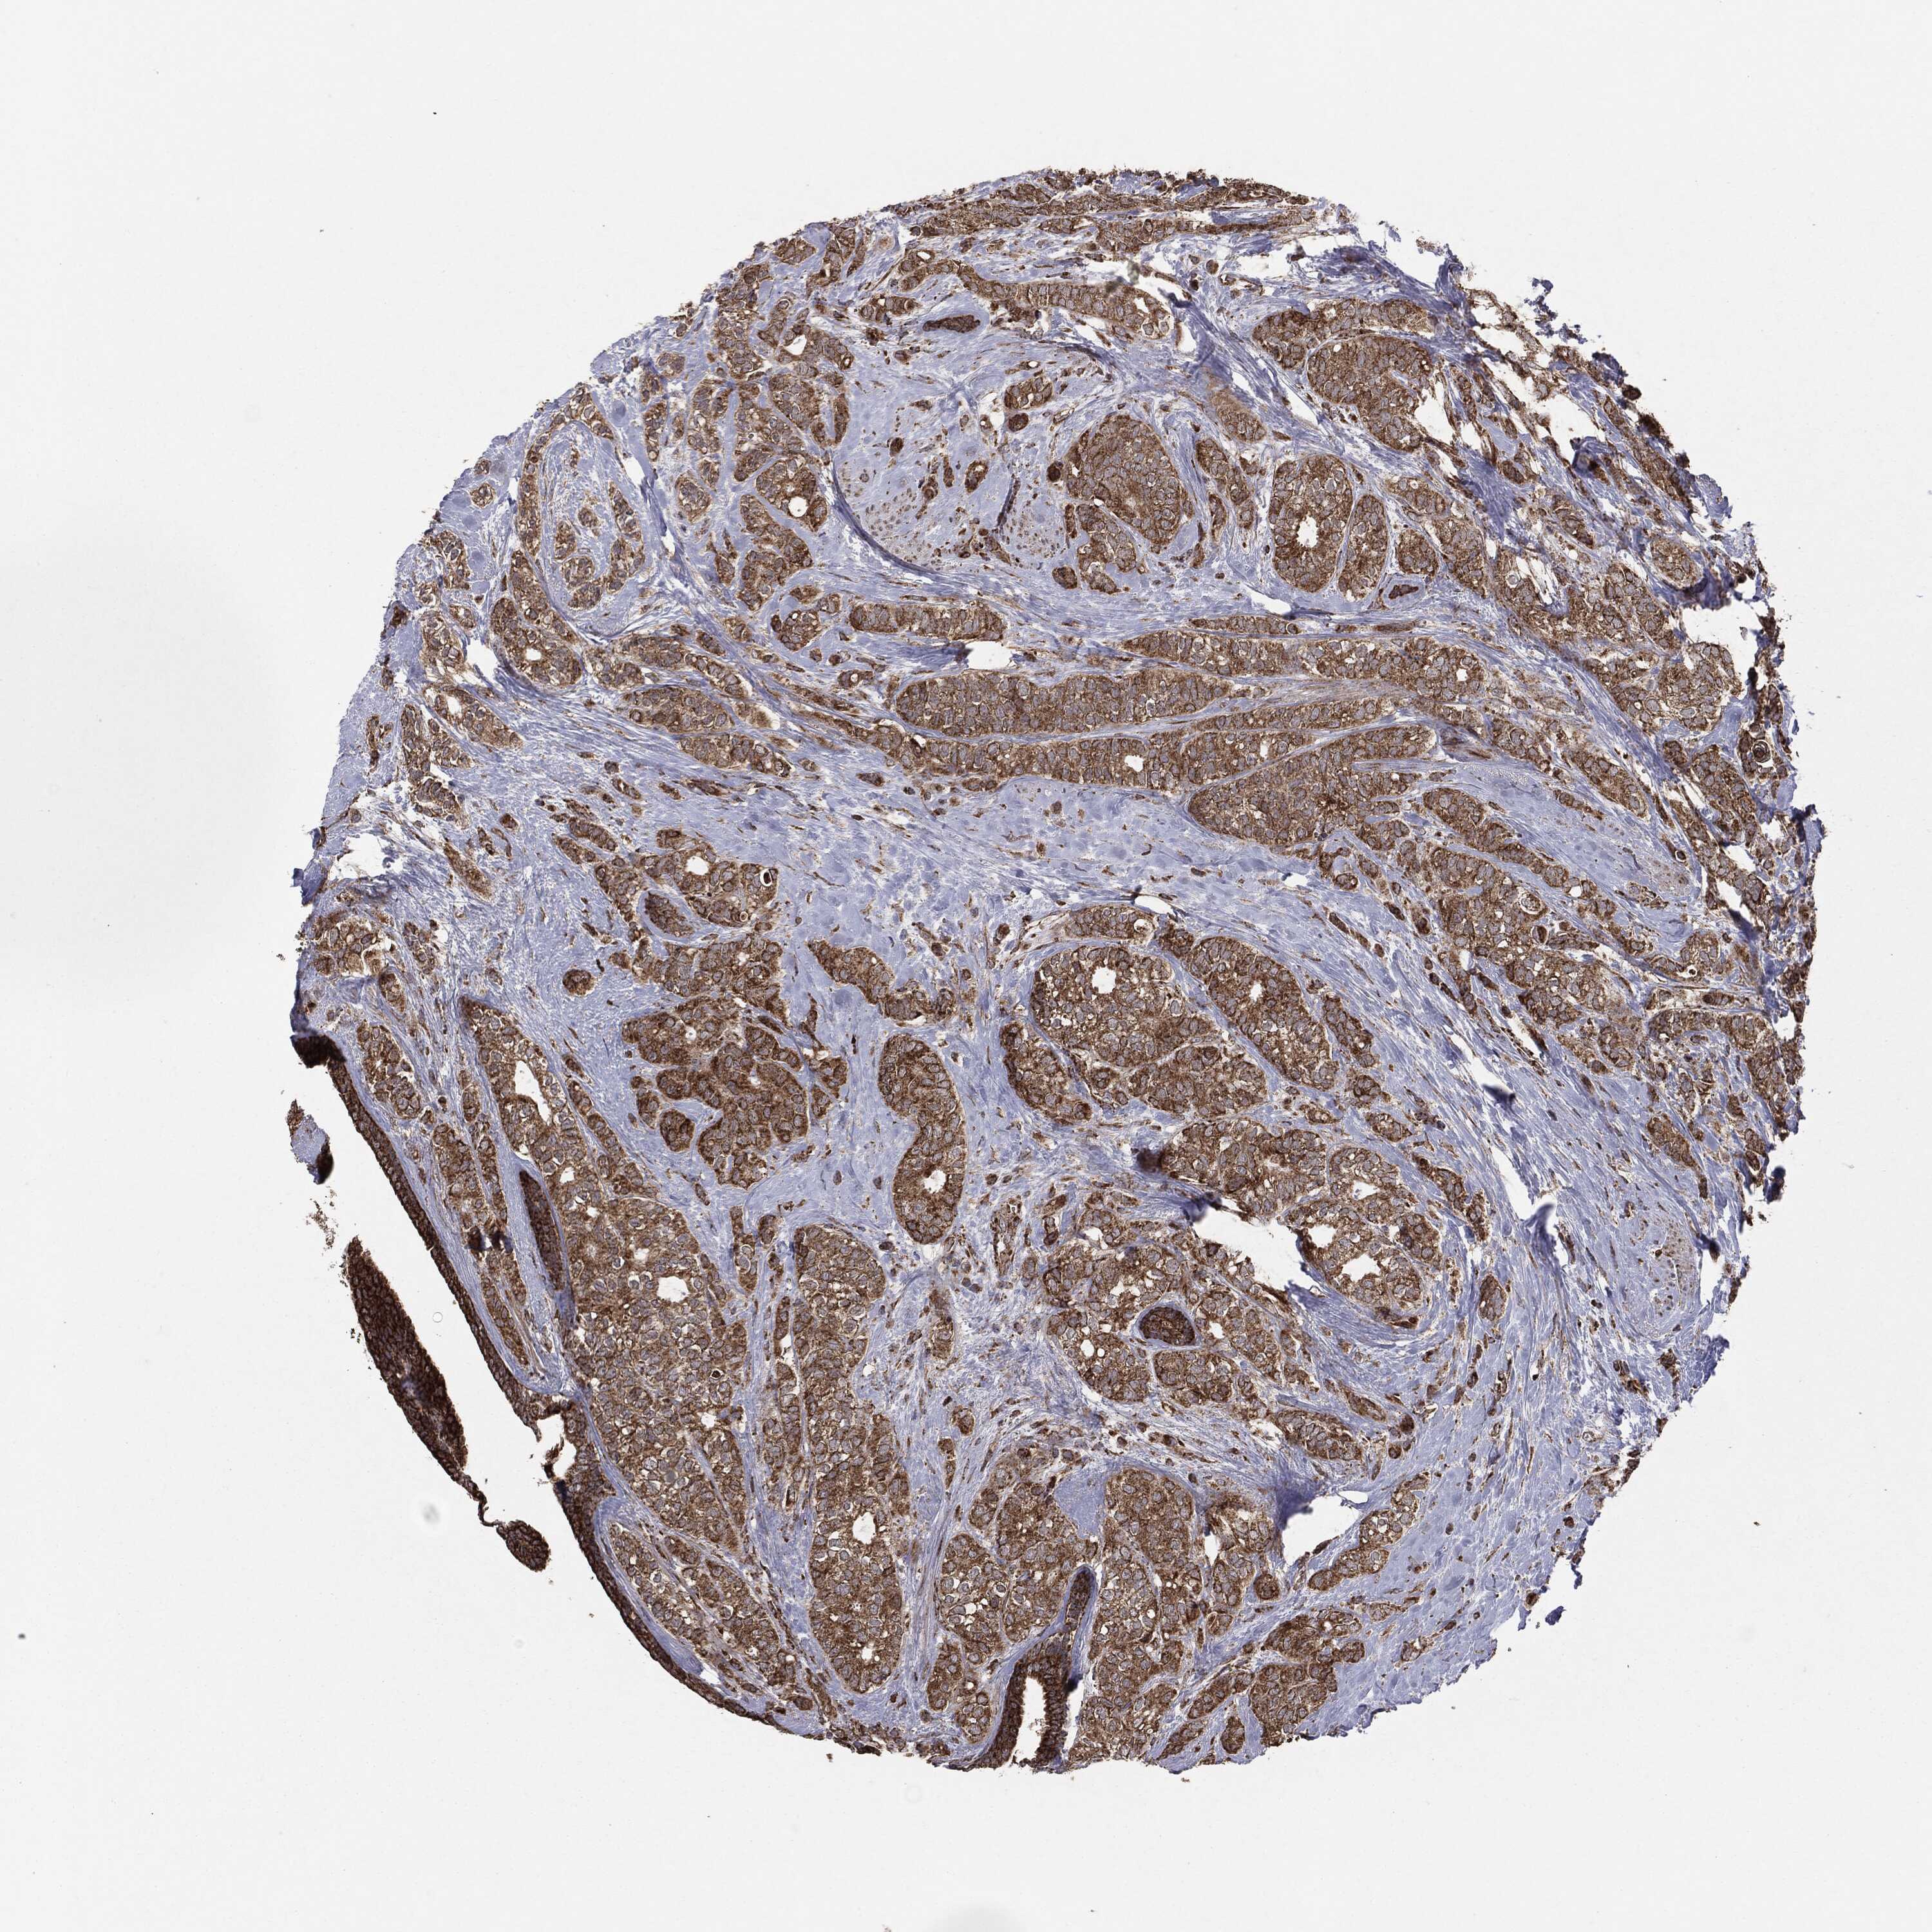

CANCER BREAST CANCER Show tissue menu

BRCA TCGA BRCA VALIDATION PROTEIN EXPRESSION